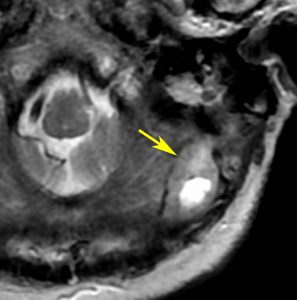

40代男性の大脳鎌テント接合部の硬膜に発生したグレード3です。激しい出血のために腫瘍摘出を部分摘出で中断せざるを得なかった例です。

この例でも,硬膜発生腫瘍ということは手術前の画像診断で解ってはいたのですが,髄膜腫と異なり不整な形をしてのう胞があり,一部は腫瘍壊死でした。